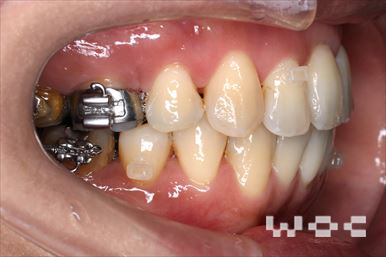

治療中1

治療中2

治療中3

治療中4

治療中5